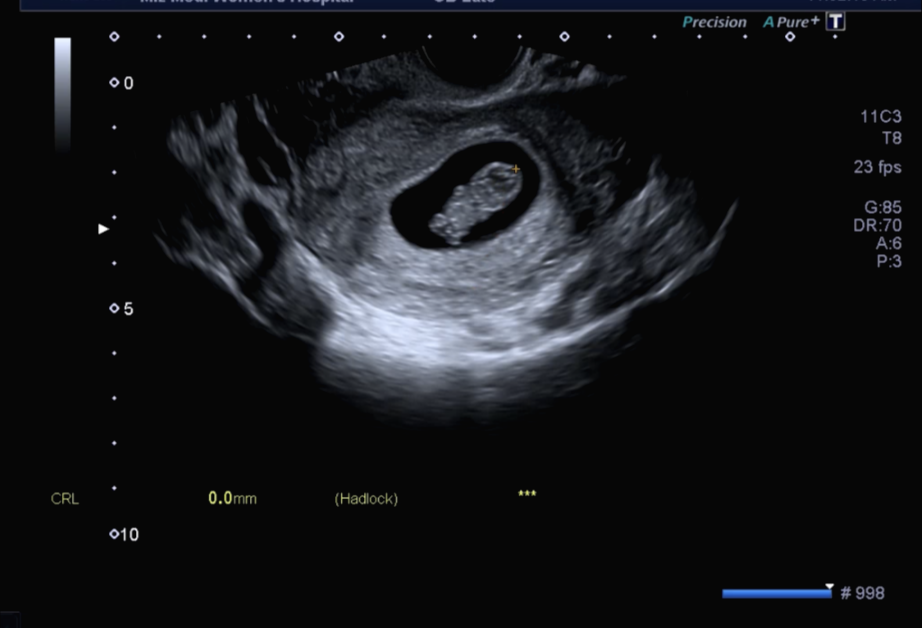

원래는 수요일이나 목요일에 방문을 했어야 하는데 업무상 해당 날짜가 안되어 조금 빠른 화요일에 방문하게 되었다. 그래서 8주 차 6일. 인터넷을 찾아보니 9주 차가 가장 젤리곰이 귀엽게 보인다고 해서 조금 아쉬웠으나 다름 귀여운 젤리곰을 만나고 왔다.

7주 차 0일에 방문했을 때는 정말 콩알만 한 아가가 보였다. 10mm 저렇게 작은 생명체에서 들리는 심장소리란 그때의 느낌은 참으로 신기했었다. 그리고 2주 만에 이렇게 머리, 몸, 팔, 다리가 보이는 아가로 성장하다니!